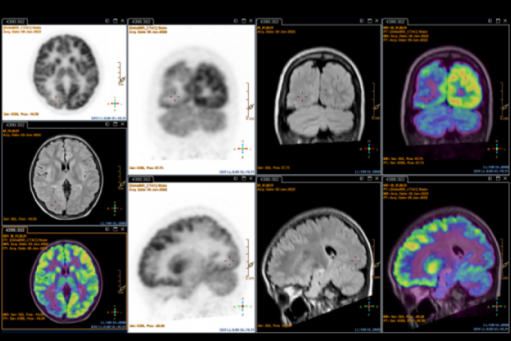

▲ 影像学检查